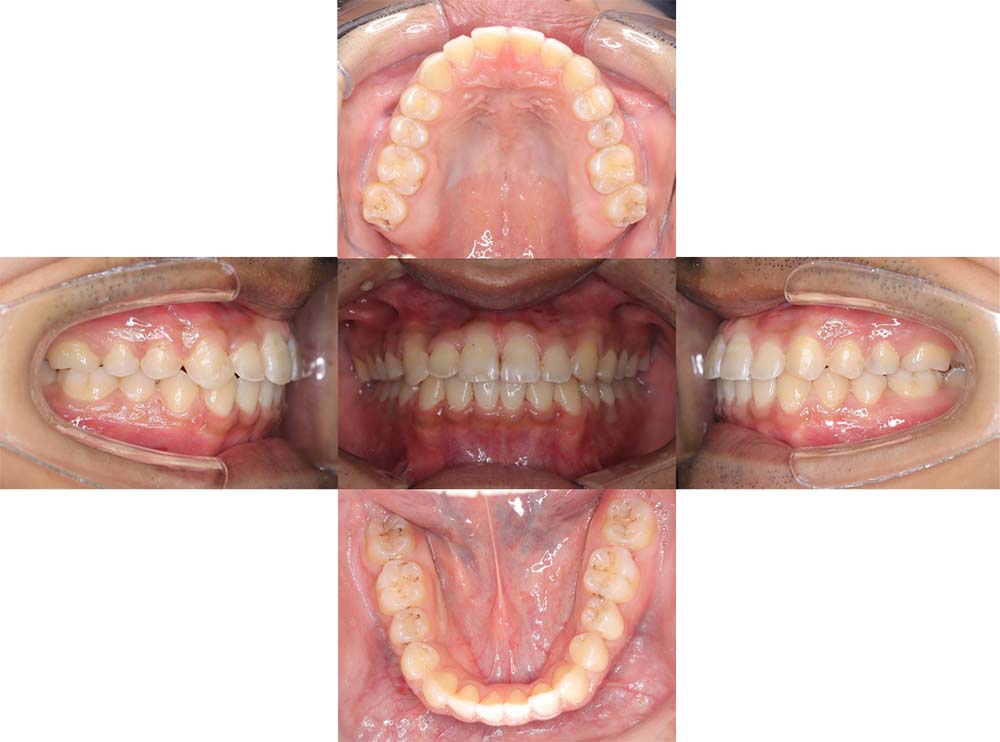

症例01

| 主訴 | 歯並びがガタガタしている。 |

| 診断名あるいは主な症状 | 叢生 |

| 年齢/性別 | 22歳・男性 |

| 矯正ステージ | 大人の矯正治療 |

| 治療方法 | ワイヤー矯正 |

| 抜歯部位/抜歯有無 | 非抜歯 |

| 治療内容 | 上顎大臼歯の遠心移動により前歯のガタガタを排列スペースを獲得し全顎的な排列を行った。 |

| 費用 | 85万円程度(2025.10時点の料金となります。) ※矯正基本料金、審美ブラケットを含む |

| 治療期間 | 2年4ヶ月 |

| 主なリスク・副作用 | 痛み、歯根吸収、歯肉退縮、虫歯、後戻り |